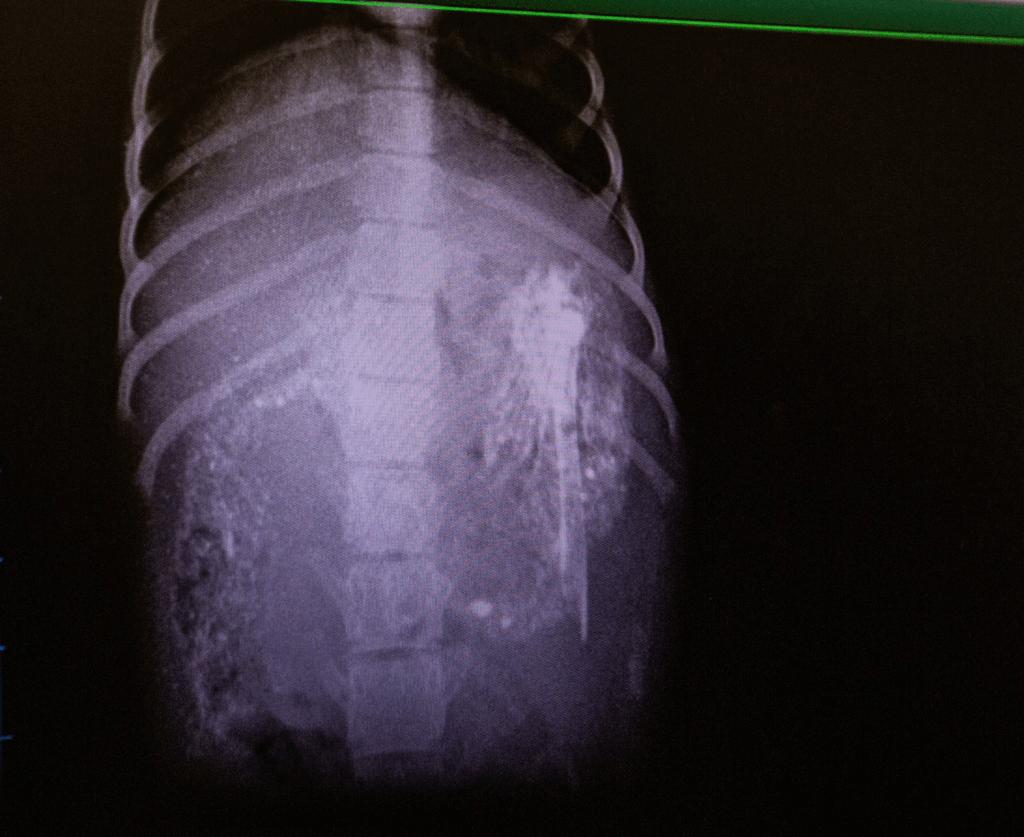

The second photo is the face you pull when the vet sees the large bone carcass precariously sitting in your stomach on an X-ray.

When observed walking, Jam also showed discomfort around his hips. An X-ray was carried out, which, thankfully, revealed no sinister reasons for the bleeding ears, however, the discovery of a large bone in his stomach that appeared to have a sharp end, caused more concern.

After rehydrating Jam, it became a precarious waiting game to see if the bone would degrade and digest on its own, as he was other ways eating fine and passing other foods, well.

With Jam’s ears clearing a week after arrival, the chicken carcass also, thankfully passed, with no internal damage caused on its way.